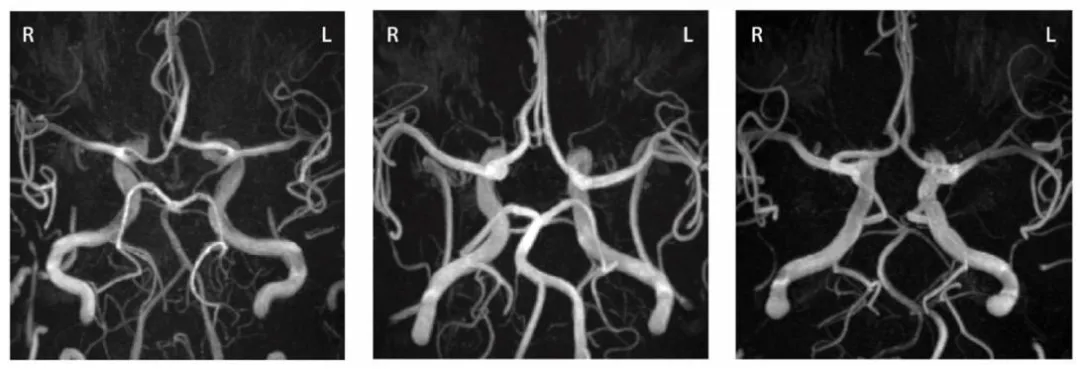

Fig. 1. Maximum intensity projections for various CoW variants using 3D TOF-MRA. Left: complete and symmetrical CoW (Lippert anterior class ‘A’ and posterior class ‘A’, seeFig. 2). Middle: Third A2 segment of the anterior cerebral artery and aplasia of both posterior communicating arteries (Lippert anterior class ‘C’ and posterior class ‘E’). Right:unilateral fetal-type posterior cerebral artery (Lippert anterior class ‘D’ and posterior class ‘J’).

图 1. 利用 3D TOF-MRA 获得的不同 Willis 环(CoW)变异型的最大强度投影图左图:完整且对称的 Willis 环(利珀特分类中,前循环为 “A” 类,后循环为 “A” 类,详见图 2)。中图:大脑前动脉存在第三 A2 段,且双侧后交通动脉发育不全(利珀特分类中,前循环为 “C” 类,后循环为 “E” 类)。右图:单侧胚胎型大脑后动脉(利珀特分类中,前循环为 “D” 类,后循环为 “J” 类)。